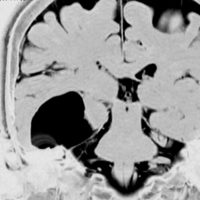

テント下くも膜のう胞

高齢の女性のくも膜のう胞です。テント下,上小脳槽にある大きなくも膜のう胞です。小脳扁桃ヘルニアになり,脊髄空洞症を併発しています。第4脳室出口の閉塞で水頭症となっていました。症状は数年かかって徐々に進行した歩行障害で,転倒しやすくなったとの主訴で受診しました。これは,のう胞壁を開頭手術で摘出する必要があるものです。数十年もある大きなのう胞ですから,意外に周囲の脳槽は狭いものです。実際に顕微鏡手術で,迂回槽と交通をつけるようにのう胞壁を除去したのですが,髄液交通を確保するのはとても難しいものでした。内視鏡ではリスクが高いかもしれません。